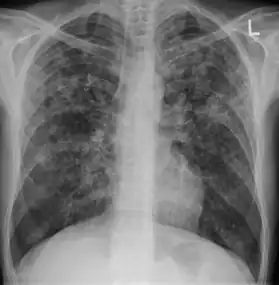

![]() | |

| Chest X ray showing miliary tuberculosis | |

Miliary tuberculosis is a form of tuberculosis that is characterized by a wide dissemination into the human body and by the tiny size of the lesions (1–5 mm). Its name comes from a distinctive pattern seen on a chest radiograph of many tiny spots distributed throughout the lung fields with the appearance similar to millet seeds—thus the term "miliary" tuberculosis. Miliary TB may infect any number of organs, including the lungs, liver, and spleen.[2] Miliary tuberculosis is present in about 2% of all reported cases of tuberculosis and accounts for up to 20% of all extra-pulmonary tuberculosis cases.[3]